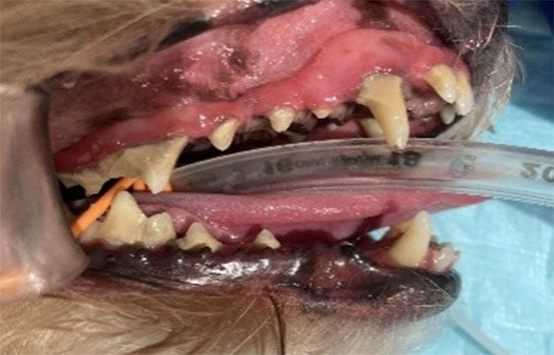

小型犬MIX、9歳6ヵ月、避妊メス

- 口臭および歯石の沈着

- ワクチン接種時に口臭の相談あり

- 身体検査上、口臭の原因として歯垢および歯石の沈着があげられ、歯石除去を推奨した。

- 全身麻酔下でスケーリングおよびポリッシングを行った。

- 右側上顎第四前臼歯部は歯周ポケットが深く歯肉炎を併発しており、出血が認められた。

- 歯肉炎のアフターフォローとしてプラズマ治療を実施した。

- 歯肉炎も改善し、自宅でのデンタルケアを継続していただいている。